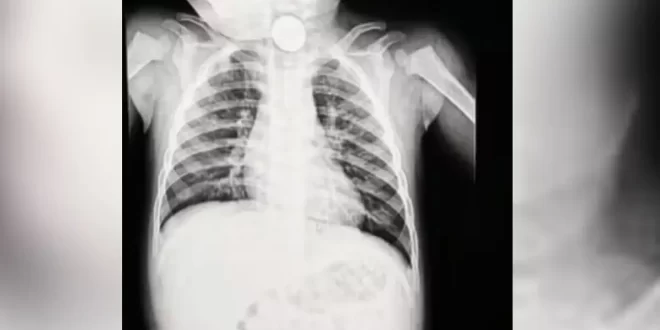

Pedro foi levado a uma unidade de saúde, onde um exame de raio-x identificou a presença de um objeto no esôfago. Inicialmente, os profissionais acreditaram que se tratava apenas de uma peça de plástico de algum brinquedo, o que fez com que o atendimento não fosse considerado urgente. Incomodados com a demora e com a piora do quadro, os pais decidiram procurar outro serviço médico.

Após novos exames, os médicos constataram que o objeto era uma bateria tipo botão, semelhante às utilizadas em relógios. A bateria foi retirada por meio de endoscopia depois de cerca de 12 horas no organismo da criança. Durante o procedimento, os profissionais identificaram sinais de necrose no esôfago e risco de perfuração, uma complicação grave que pode evoluir para infecção generalizada.